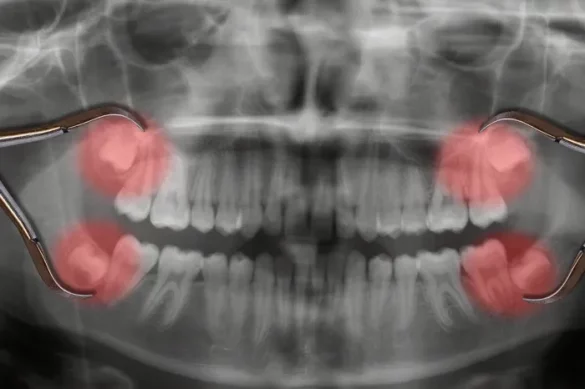

Wisdom teeth removal, especially when the teeth are impacted, is often considered the most painful dental extraction. Several factors contribute to this increased pain and discomfort:

Location and Accessibility

Wisdom teeth are positioned far back in the mouth. Their location makes them harder to reach and remove, often requiring prolonged procedures and more force. This can result in increased soreness and trauma to surrounding tissues.

Impaction

Many wisdom teeth do not emerge completely. When teeth are trapped in the jawbone or gum tissue (impacted), their removal usually involves cutting through both gum and bone. This necessity for surgical extraction increases the complexity and potential for pain.

Proximity to Nerves

Lower wisdom teeth are located near major nerves in the jaw. Operations in this area carry a higher risk of nerve irritation, which can cause numbness, tingling, or even extended pain following surgery.

Bone Removal

In many cases, some jawbone must be removed to fully access and extract the impacted tooth. Removing bone adds trauma, increases swelling, and generally causes more discomfort than extracting non-impacted teeth.